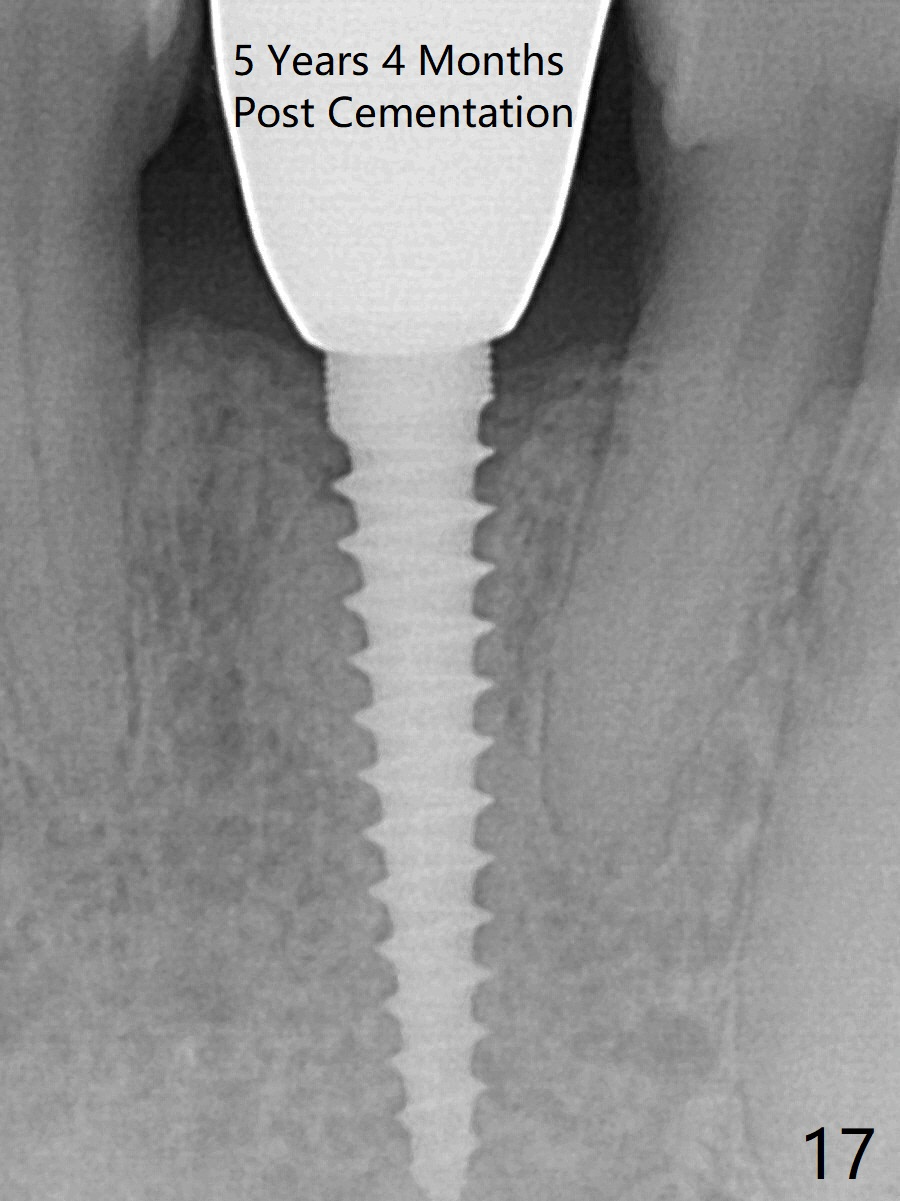

Fig.10,11 show 7 day follow up. The permanent crown is seated 4.5 months postop (Fig.12). Minimal bone resorption occurs at the crest 4 months postop (Fig.13), which is most likely associated with conservative approach (flapless). The patient returns for follow up 2.5 months post cementation (Fig.14,15). The implant remains in the bone 4 years post cementation (Fig.16 CT coronal section; lingual thread exposure, corresponding to preop defect in Fig.1). There is mild coronal bone resorption 5 years 4 months post cementation (Fig.17).